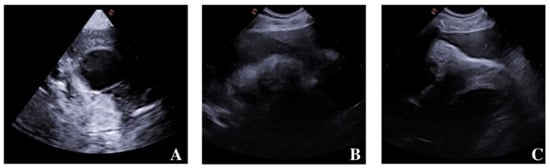

2.2. Diagnostic Imaging